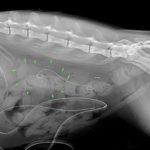

たった1mmの大きさの尿管結石でも猫の尿管を閉塞してしまうことがあります。血液検査、尿検査、超音波検査、無麻酔CT検査などで外科的に対応すべきか?詳しく評価します。閉塞してもすぐには腎盂の拡張はそれほど顕著ではありませんし、片側のみであれば血液検査に異常値が検出されないこともしばしばです。マイクロサージェリーで短尺ステントと尿管新吻合術で対応しました。通常はシュウ酸カルシウムであり溶解できないので非常に厄介です。